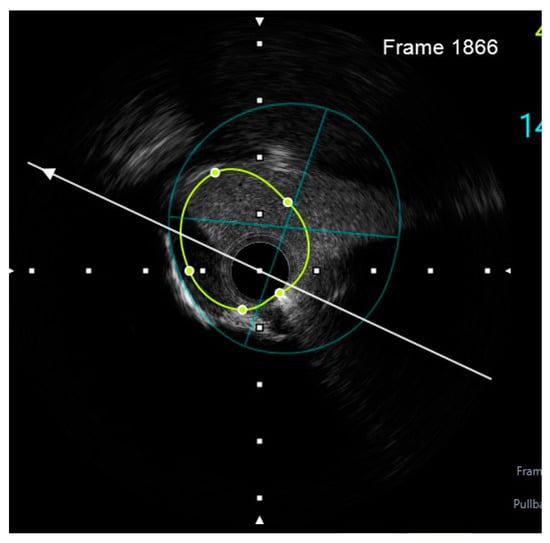

- Engage the left coronary artery with an EBU 4.0/8F guiding catheter. Wiring the three branches of the trifurcation (Floppy guide wires in LAD and RI, Hydrophilic guide wire in LCX) (Figure 14).